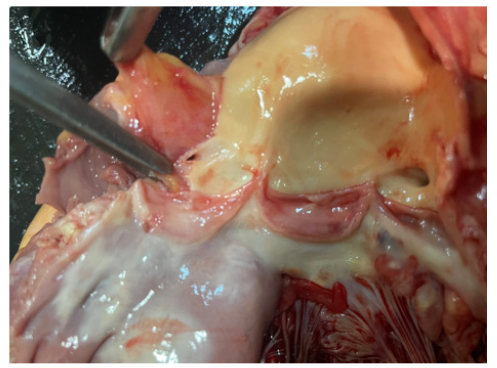

Figures 10a-10b show the size of aneurysm. The aneurysm of Sinus of Valsalva was filled with water to measure the size; it was 4.2 X 5.6 cm in diameter. It was located next to left coronary ostia (Figures 11-13).

Figure 10a: The aneurysm of Sinus of Valsalva was filled with water to measure the size revealing 3.2 X 3.6 cm in diameter. It was located next to left coronary ostia.